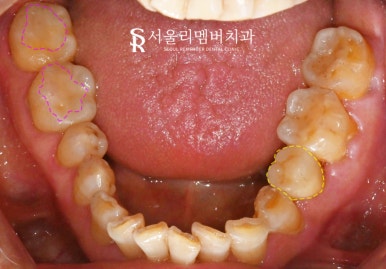

2024.12.03

이 케이스에서도

임플란트 수술 후 치유 기간 동안

환자의 일정에 맞추어

나머지 부위도 함께 해드렸습니다.